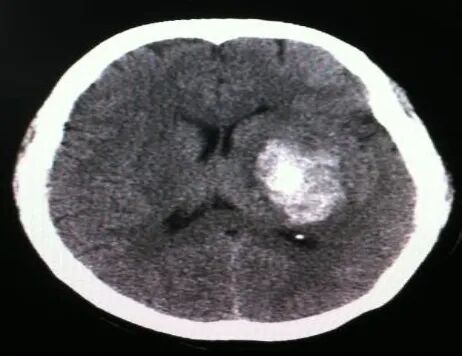

干细胞为脑出血后遗症的康复带来希望

脑出血,俗称“脑溢血”,属于中枢神经系统损伤,是指非外伤所导致的脑实质出血,由自身原因引起的脑内血管自发性破裂,从而造成脑内出血。脑出血具有“发病迅猛、且没有预兆、病情凶险、变化快、复发率高、高致残率和死亡率”的特点,早期死亡率很高,急性期的病死率可达30%~40%,幸存的患者会留有多种不同程度的后遗症,如昏迷、偏瘫、认知障碍、语言障碍、吞咽障碍等。

我国是世界上脑出血疾病发病率较高的国家,中老年人是脑出血发病的主要人群,以40—70岁为最主要的发病年龄,且越来越年轻化,秋冬季尤甚,是目前中老年人主要致死性疾病之—,脑出血已成为严重的社会问题和医学难题。